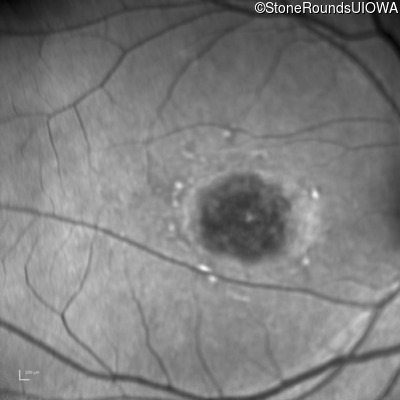

Infrared Fundus Photograph - Left - 20/100

Exemplar